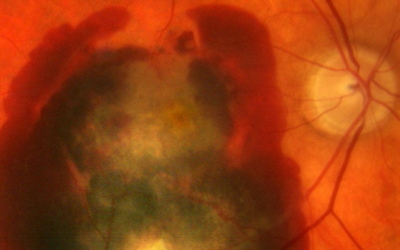

¿Qué son las drusas maculares?

¿Qué son las drusas maculares? Si le han diagnosticado degeneración macular (DMAE), es probable que haya escuchado a su oftalmólogo decir algo acerca de ver algunas drusas durante el examen ocular. De hecho, el desarrollo de estos depósitos amarillos son los primeros...